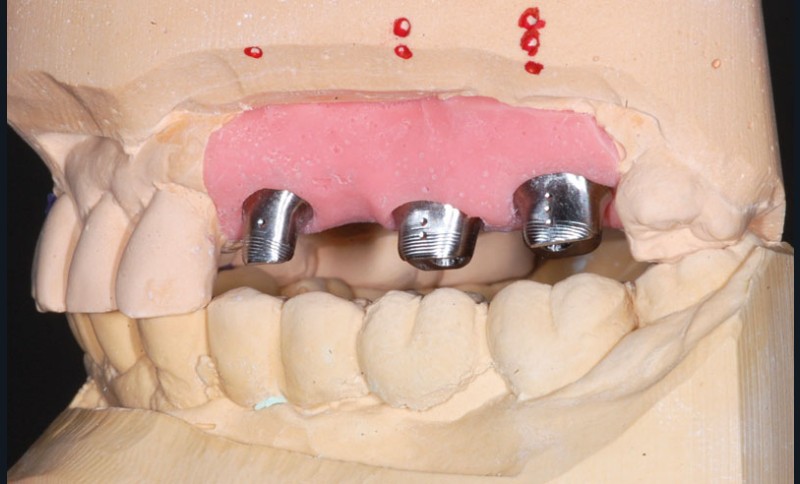

Le modèle de travail est fabriqué au laboratoire, des piliers CFAO Atlantis™ sont réalisés en fonction du bridge antagoniste transitoire.

Le bridge 24-26 céramométallique et la couronne unitaire sur 27 sont réalisés. Les piliers CFAO sont transvissés sur les implants, puis les éléments céramo-métalliques sont posés. Le résultat montre un parfait respect du projet prothétique en fonction de la courbe occlusale obtenue avec le bridge transitoire réalisé avec le ProtempTM 4 et une adaptation parfaite.